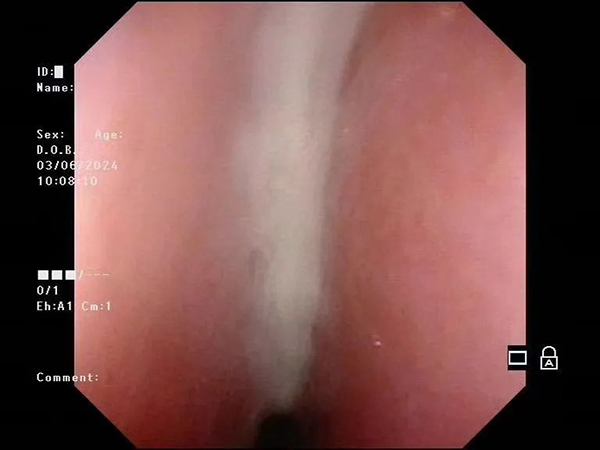

镜下影像示例:

镜下小儿腺样体肥大